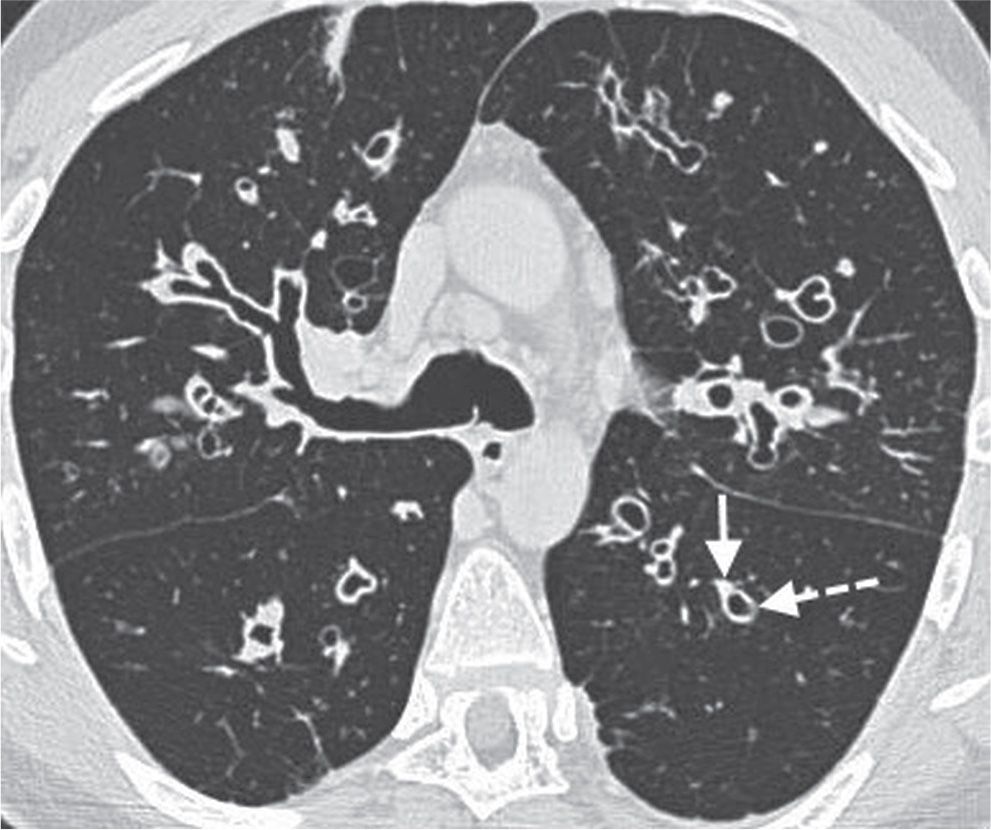

Highresolution computed tomography (HRCT) images of the lung. (A) HRCT Rings Around Lungs In this condition, part of the body's main artery or its branches form a ring around the windpipe,. Pneumothorax in the supine position shows different. The signet ring sign is seen in bronchiectasis when the dilated bronchus and accompanying pulmonary artery branch are seen. Thoracic abnormal air collects in multiple thoracic spaces, including the pleural cavity, chest wall, mediastinum, pericardium,. Rings Around Lungs.

Signs and Patterns of Lung Disease Radiology Key Rings Around Lungs Thoracic abnormal air collects in multiple thoracic spaces, including the pleural cavity, chest wall, mediastinum, pericardium, and lung. That means it's a congenital heart defect. The signet ring sign is seen in bronchiectasis when the dilated bronchus and accompanying pulmonary artery branch are seen. Vascular rings are congenital vascular anomalies of the aortic arch system which compress the esophagus and. Rings Around Lungs.

Signs and Patterns of Lung Disease Radiology Key Rings Around Lungs Gas may originate from the lungs, trachea, central bronchi,. Pneumomediastinum is the presence of extraluminal gas within the mediastinum. A vascular ring is a heart problem present at birth. Vascular rings are congenital vascular anomalies of the aortic arch system which compress the esophagus and trachea. That means it's a congenital heart defect. The signet ring sign is seen in. Rings Around Lungs.